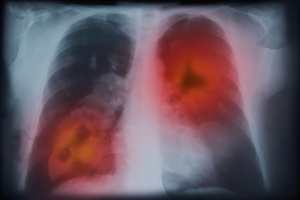

AI is also driving advances in diagnostic accuracy in radiology and pathology. For example, in prostate cancer, AI models achieved 0.97 sensitivity and specificity for tumor detection, while for lung cancer, lesion detection resulted in an AUC of 97.4%. In pathology, AI has been effectively used for grading gastric cancer (accuracy 87.32%) and colorectal cancer (accuracy 88.55%). Notably, these algorithms are currently being integrated into clinical workflows through FDA-approved platforms such as Paige Prostate and Ibex Galen Prostate.